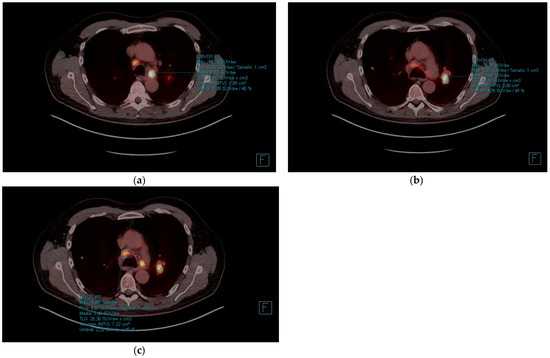

| PET-CT | October 2021 | Re-evaluation | - Hypermetabolic mass (SUVmax 24.72) in left lower lobe of 4.2 × 3.5 cm. - Complete response of the hilar adenopathies, without pathologic uptake. - Focal increase of FDG in pseudonodular formations in mesenteric fat, up to SUVmax 12.48, in relation to mesenteric panniculitis. |

| PET-CT | October 2022 | Re-evaluation | - Morphometabolic progression of pathologic adenopathies observed on staging PET in March 2021 that had normalized in October 2021, SUVmax 19.5. - Complete morphometabolic response of primary left lower lobe neoplasm, currently 1.8 cm and SUVmax of 2.6. - Signs of mesenteric panniculitis, with practical metabolic normalization of the FDG uptake foci at this level that were visualized in the previous PET scan of Oct/21. |

| PET-CT | April 2023 | Severe abdominal pain that had consulted 4 times in the emergency room | - Hypermetabolic persistence of adenopathies in the right cervical chain, lower paratracheal and right pulmonary hilum with dissociated response, some have progressed and others have improved. - Signs of mesenteric panniculitis, visualizing increased pseudonodular formations, several with FDG uptake up to SUVmax 7.50, not present in the previous study. |